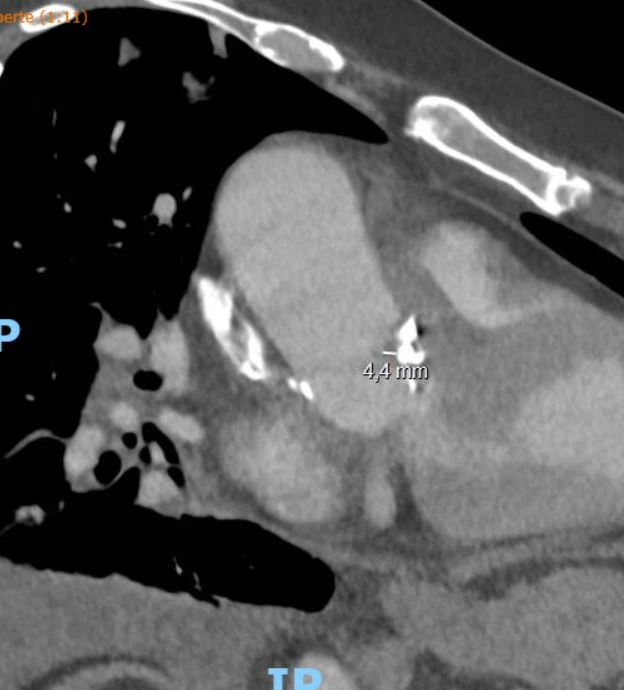

Un patient de 64 ans, connu pour un diabète de type 2 NIR et une HTA, est amené aux urgences pour un état de choc. Il se plaint d’une baisse d’état général associée à une dyspnée d’effort depuis plusieurs jours. A son arrivée, il est hypotendu, tachycarde et fébrile. Le status met en évidence un souffle épigastrique connu.

Le laboratoire montre un syndrome inflammatoire, une IRA ainsi qu’une hyperlactatémie à la gazométrie. La radiographie du thorax est sans particularité. Après quelques heures, les hémocultures sont positives pour un bacille Gram négatif.

Quelle investigation fais-tu en priorité ?